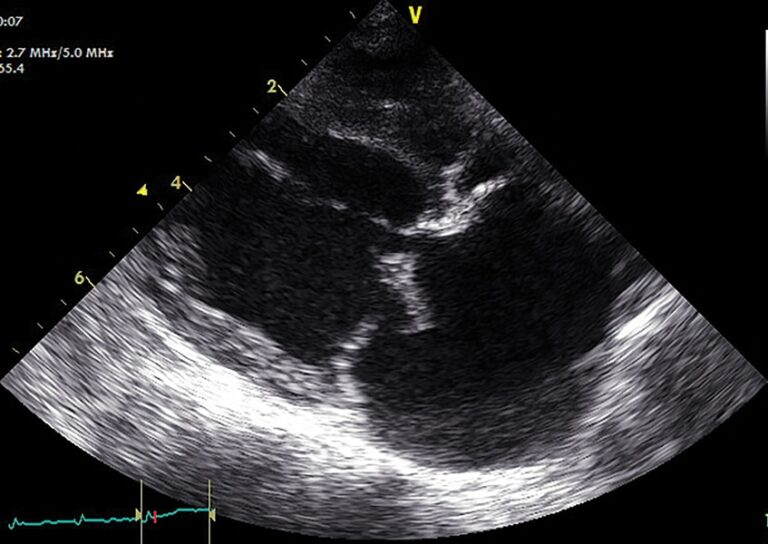

Figure 2 - Echocardiogram showing mitral valve regurgitation with color Doppler flow and left atrial enlargement in a dog with MMVD. Image credit: https://todaysveterinarypractice.com/cardiology/congestive-heart-failure-in-dogs/

- Echocardiography: Thickened, prolapsing mitral valve leaflets; mitral regurgitation on color Doppler; LA/Ao ratio greater than or equal to 1.6 indicates significant enlargement

Echocardiography

Echocardiography is the gold standard for diagnosing underlying cardiac disease and assessing severity.

| LA/Ao Ratio | Greater than or equal to 1.6 | Left atrial dilation from volume overload |

| LVIDdN | Greater than or equal to 1.7 | Left ventricular dilation |

| Fractional Shortening | 25-45% (normal) | Low FS indicates systolic dysfunction (DCM) High FS in MMVD from volume overload |

- Figure 2: Color Doppler echocardiogram showing mitral regurgitation. Source: Today's Veterinary Practice - "Congestive Heart Failure in Dogs: Treatment and Management" - Figure 4. Available at: https://todaysveterinarypractice.com/cardiology/congestive-heart-failure-in-dogs/ (Open access educational content)